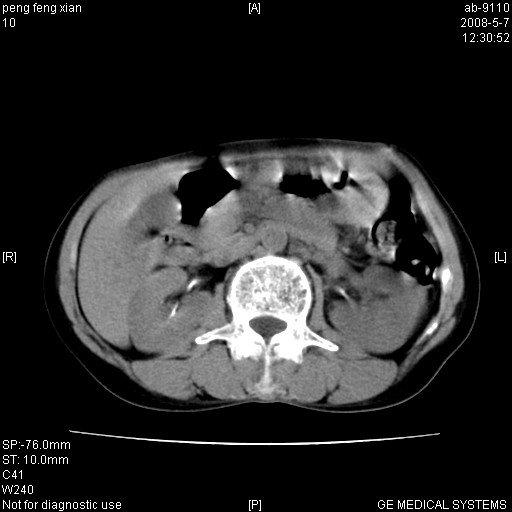

女,56岁。b超左一腹包块,考虑胃肠道肿瘤。

结肠病变?建议行全消化道检查!

胃癌并转移。

胃体部胃壁增厚,不均匀性强化,与胰腺分解欠情.

考虑:胃癌,胰腺受侵待除外.